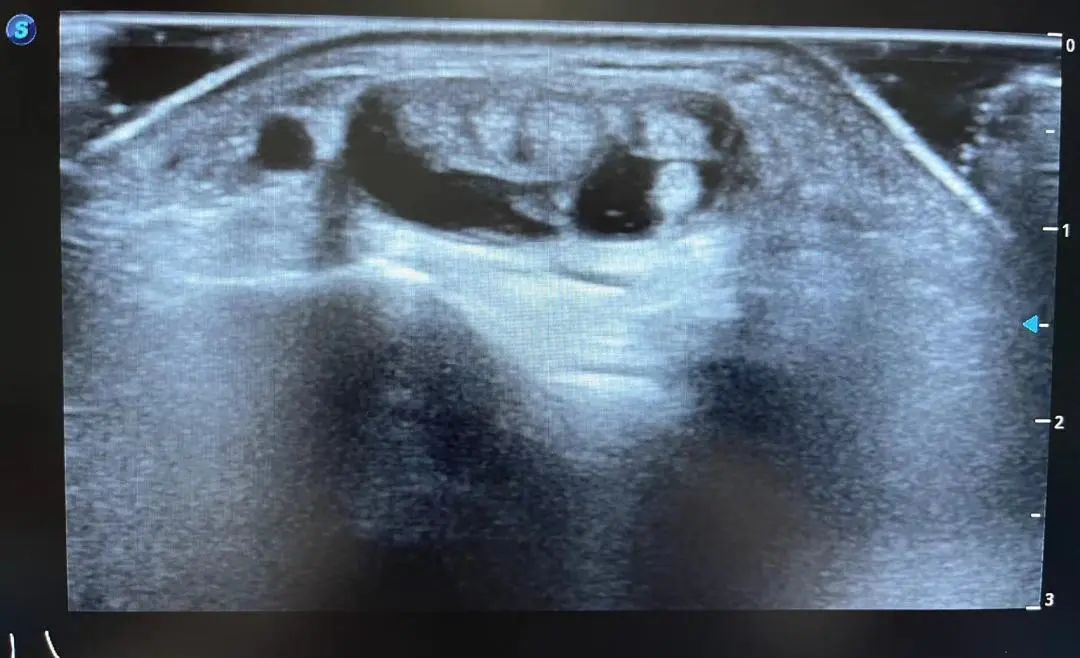

患者2:男 69岁 因疼痛行走困难来院检查,经肌骨超声检查发现该患者膝关节滑膜增生伴积液。